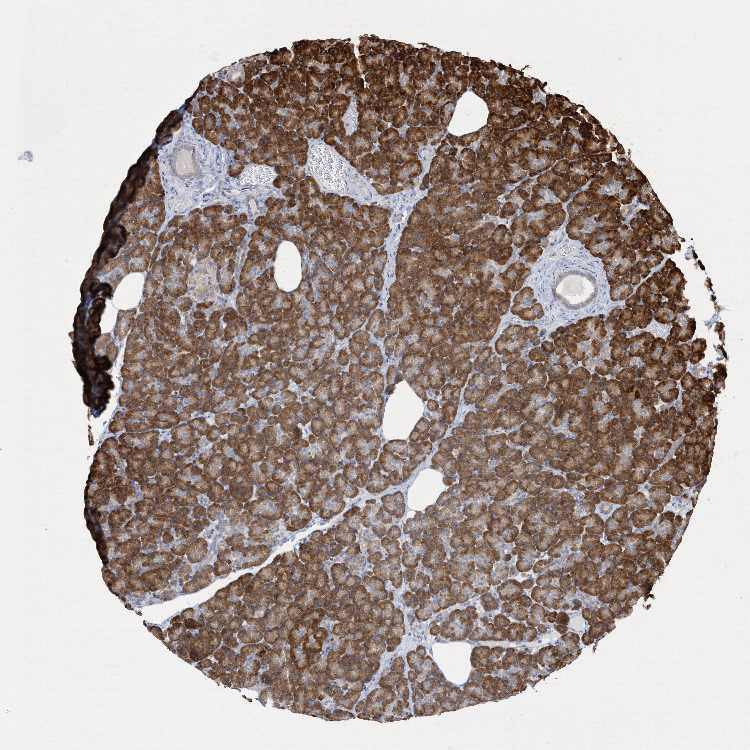

Antibody HPA035947

Exocrine glandular cells High

Pancreatic endocrine cells Not detected